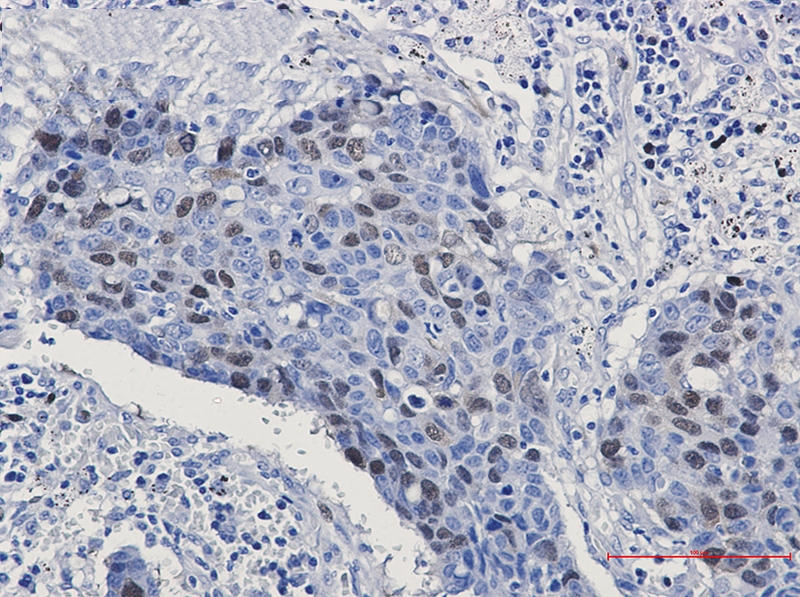

Immunohistochemistry of Cyclin A2 in paraffin-embedded Human lung cancer tissue using Cyclin A2 Rabbit mAb at dilution 1/50